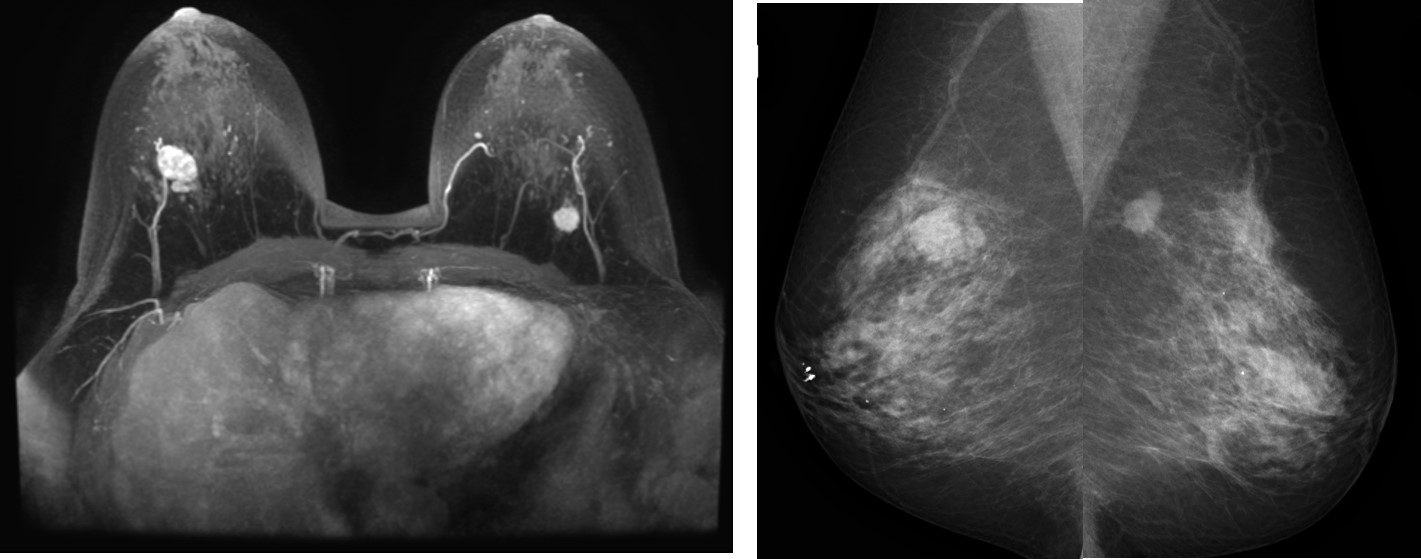

• マンモグラフィ) 乳房の構成:乳腺散在

右外上に分葉状・境界明瞭な腫瘤(等~高濃度)。

左U域に不整形・境界不明瞭な腫瘤、spiculaも疑う。CCは範囲外。

右カテゴリー3、線維腺腫 疑い

左カテゴリー4、浸潤性乳管癌 疑い

• 左腫瘤

円形・境界不明瞭で、内部不均一なfast-washout pattern*を呈する

• 右腫瘤

造影で内部均一、漸増型*

Dark internal septationがある

背側に分葉状の部分がある

右 BI-RADS カテゴリ-4

( 4A程度、2-10%の悪性の可能性)

線維腺腫、葉状腫瘍の疑い

左 BI-RADS カテゴリ-5

(95%以上悪性を考える)

浸潤性乳管癌の疑い